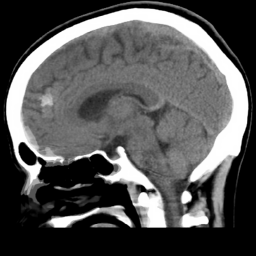

Slices Descriptions

(a) [Uncaptioned image] This image is a coronal CT scan of the chest, displaying the lungs, heart, and surrounding anatomical structures. The lungs appear as large, dark areas on either side of the image, with visible branching airways. The heart is centrally located, appearing as a lighter, more solid structure. The spine is visible in the background, running vertically along the center. The ribs are seen as curved, lighter lines on either side of the chest. There are also various soft tissues and blood vessels visible. The scan provides detailed cross-sectional imaging, useful for diagnosing and evaluating thoracic conditions.

(b) [Uncaptioned image] This image is a coronal MRI scan of the brain, providing a crosssectional view of the cerebral structures. The scan clearly shows the symmetrical arrangement of the brain’s hemispheres, with the central sulcus and other gyri and sulci visible on the surface. The ventricular system is also apparent, with the lateral ventricles appearing as dark, butterfly-shaped structures in the middle. The surrounding gray matter and white matter can be distinguished by their varying shades of gray. This type of imaging is crucial for diagnosing and evaluating neurological conditions, as it highlights differences in tissue density and structure within the brain.

(c) [Uncaptioned image] This image is a sagittal MRI scan of the thoracic region, prominently displaying the heart and surrounding structures. The heart is centrally located, with its chambers and major blood vessels visible, including the aorta. The lungs, with their branching bronchial structures, can be seen around the heart. The vertebral column runs vertically along the left side of the image, providing structural support and orientation. The grayscale contrast highlights different tissue densities, aiding in distinguishing between various anatomical features. This detailed imaging is crucial for diagnosing cardiovascular and thoracic conditions.

(d) [Uncaptioned image] This image is a transverse CT scan of the abdomen, offering a detailed cross-sectional view of the internal organs. The large, rounded structure in the center is likely the liver, with its distinct texture and density. Adjacent to it, the stomach and spleen are visible, with the spleen showing a brighter area indicative of different tissue or a lesion. The vertebral column is centrally located at the bottom, providing a structural reference. The grayscale contrast differentiates between various tissue densities, essential for identifying abnormalities. This detailed imaging is crucial for diagnosing abdominal conditions and guiding further medical evaluation and treatment.

(e) [Uncaptioned image] This image is a sagittal MRI scan of the abdomen, showcasing various internal structures in detail. Central to the image is a large, circular organ, likely the liver, with its characteristic texture and surrounding tissues. The diaphragm is visible, delineating the boundary between the thoracic and abdominal cavities. The vertebral column is seen running vertically along the left side, providing a reference point for orientation. The grayscale contrast highlights different tissue densities, facilitating the diagnosis and evaluation of abdominal conditions.